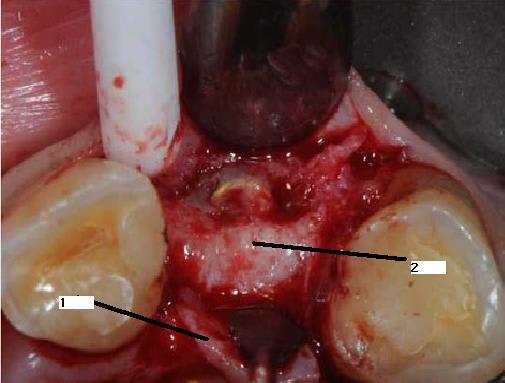

en zone 2, c'est de l'os

je profite de l'occasion pour vous montrer la cicatrisation gingivale autour de 22 à j+15